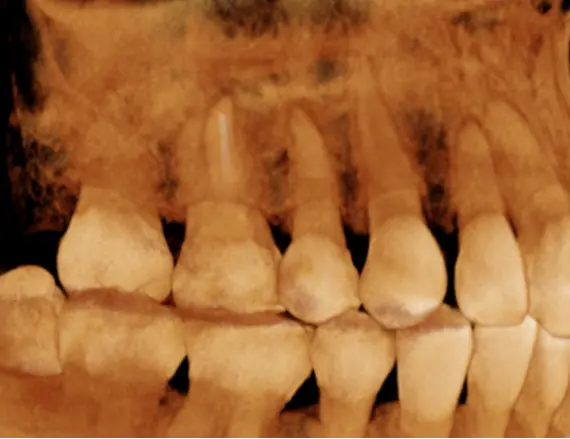

TOMOGRAFÍA DE IMPLANTES

Cuando es necesario evaluar las condiciones óseas de los rebordes alveolares.